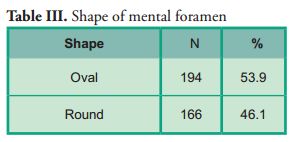

Oval was the most frequent shape, and no significant differences were observed compared with the contralateral side (p*0.057) (Table III).

Oval was the most frequent shape, and no significant differences were observed compared with the contralateral side (p*0.057) (Table III).

Regarding the shape of the mental foramen, there are several studies whose results do not agree on the classification of shapes itself. However, other studies take the oval and round shapes as evaluation criteria. These studies (4, 6, 11, 12, 15, 22) show an oval shape in most cases, which is consistent with the present study. However, other authors (14, 16, 20, 24) disagree with our results as they report that the round shape is the most frequent one.

Regarding the shape of the mental foramen, there are several studies whose results do not agree on the classification of shapes itself. However, other studies take the oval and round shapes as evaluation criteria. These studies (4, 6, 11, 12, 15, 22) show an oval shape in most cases, which is consistent with the present study. However, other authors (14, 16, 20, 24) disagree with our results as they report that the round shape is the most frequent one.